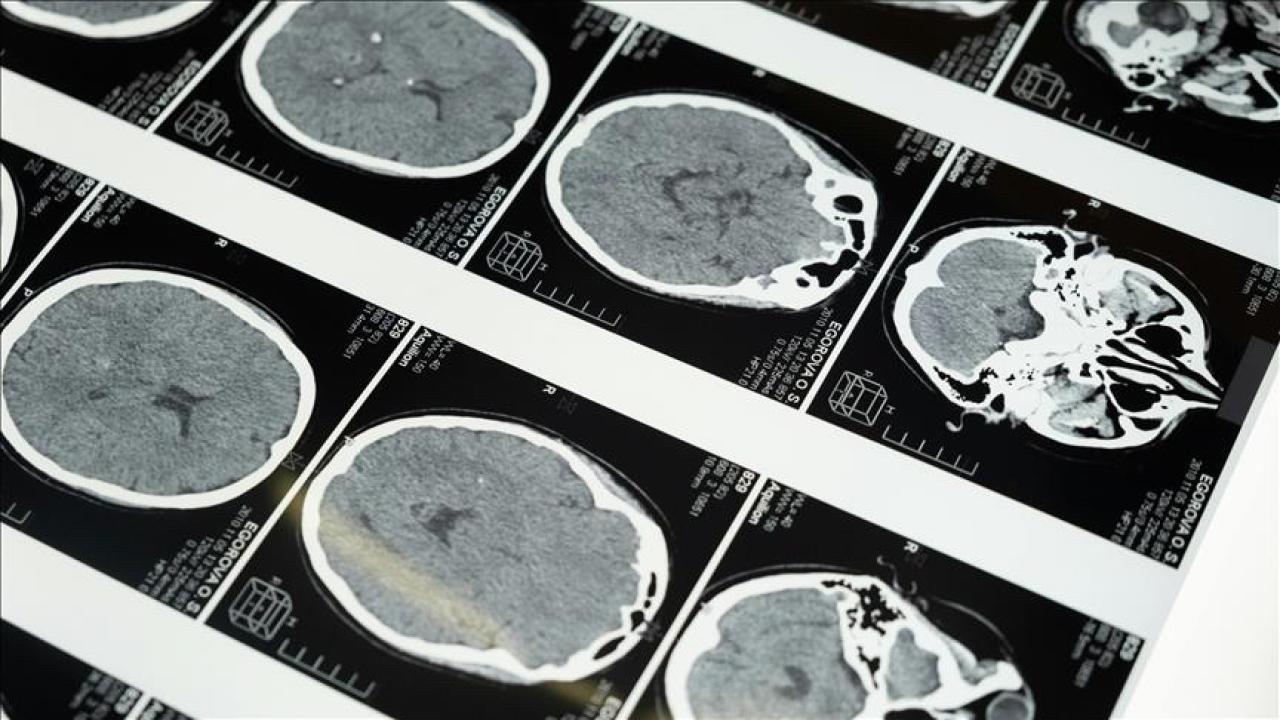

“Özellikle pıhtıyla tıkanan beyin damarının açılmasıyla ilgili stratejiler gelişti. İnmede erken dönemde yapılan damar açma tedavileri konusunda ülke olarak iyi durumdayız. İnme tedavisinde pıhtıyla tıkalı beyin damarının anjiyo yoluyla açılması mümkün. Böylelikle hastanın 3 ay sonra, 1 yıl sonra kendi işini yapabilecek hale getirilmesi sağlanabiliyor. İnme merkezlerinde uygulanabilen bu işlemi ilk 24 saat içerisinde belirli hasta gruplarına yapabiliyoruz. İlk 24 saat çok kritik, bu müdahaleler de sadece inme merkezlerinde yapılabiliyor.”